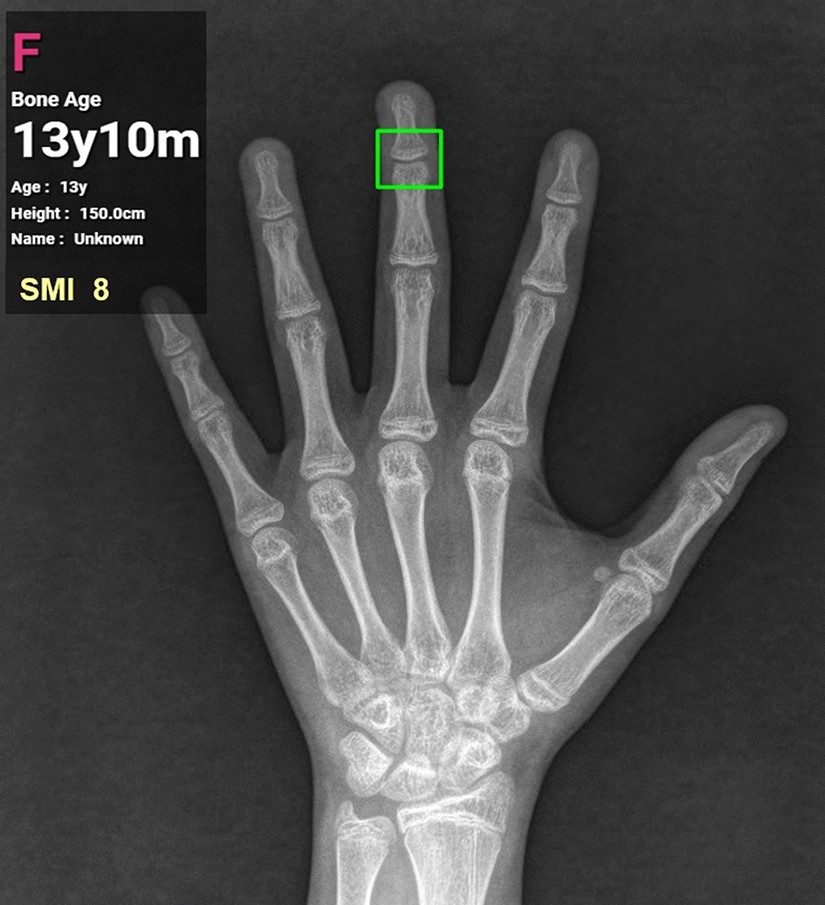

Result screen displaying the SMI stage and bone age predicted by the SMI-modified automated skeletal maturation assessment system.

From: Prediction of Fishman’s skeletal maturity indicators using artificial intelligence